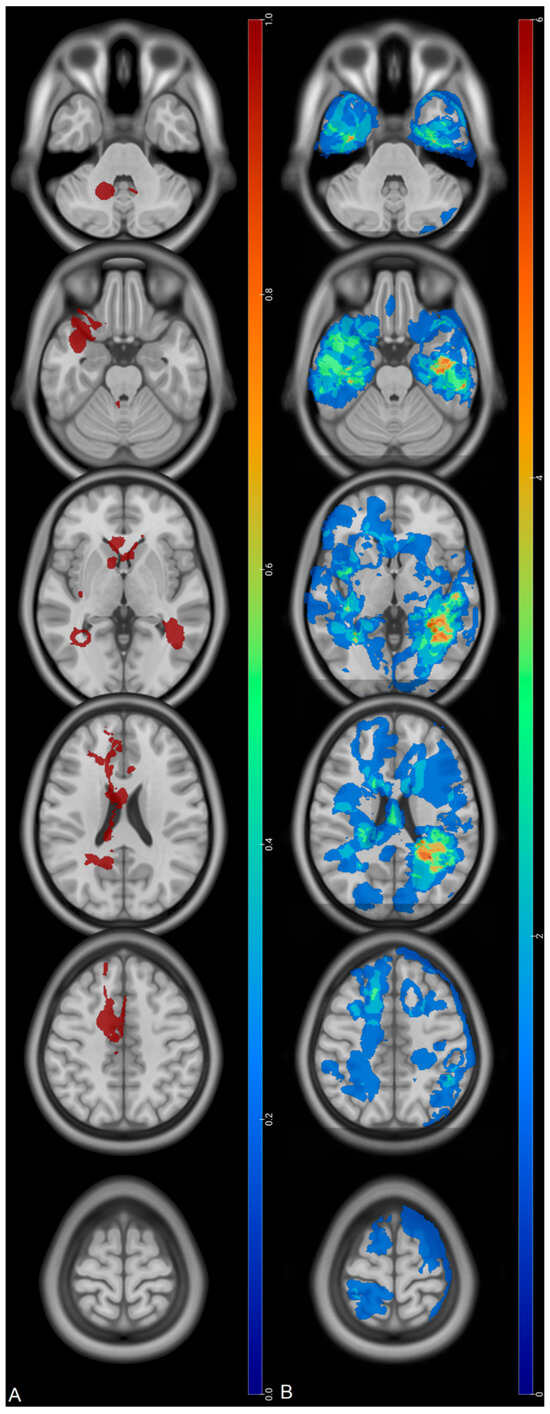

Prognostic Factors of IDH Wild-Type Glioblastoma After Extensive Surgery: A Multimodal Atlas of Tumor Locations, Recurrences and Management

by Hajar Selhane, Tiphaine Obara, Guillaume Vogin, René Anxionnat, Guillaume Gauchotte, Luc Taillandier, Marie Blonski and Fabien Rech

Cancers 2026, 18(1), 63; https://doi.org/10.3390/cancers18010063 - 24 Dec 2025

Introduction: Glioblastomas have poor prognosis despite aggressive treatment. Patterns of recurrence and overall survival (OS) can be very different. The population with complete resection having a so-called good prognosis can nevertheless present poor OS. Our purpose was to assess the OS and patterns [...] Read more.

Introduction: Glioblastomas have poor prognosis despite aggressive treatment. Patterns of recurrence and overall survival (OS) can be very different. The population with complete resection having a so-called good prognosis can nevertheless present poor OS. Our purpose was to assess the OS and patterns of recurrence thanks to multimodal statistical maps in glioblastoma with large extent of resection (residue < 10 mL). Methods: adult patients presenting IDH wild-type glioblastoma between 2013 and 2019 were selected. Clinical data and MRI characteristics were collected. Preoperative, postoperative, and recurrence volumes were segmented and normalized in the MNI space to compute statistical maps. Log-rank test and Cox model were used to assess OS and prognosis factors. Results: 60 patients were included. Mean residual volume was 0.89 ± 2 mL. Median OS was 22.3 months (95% CI: (20–35)). Initial location in the corpus callosum was associated with low OS (317 vs. 783 days, HR = 0.46, p = 0.003). At recurrence, KPS > 90 and tumor volume < 10 mL were associated with higher OS (p =0.006 and p = 0.05). Tumor contact with the SVZ as well as multifocal recurrence did not show any impact on the OS. Conclusions: High OS can be obtained thanks to surgery with residual volume < 10 mL. Invasion of the corpus callosum at diagnosis is associated with a poor prognosis despite a large extent of resection. Results suggest that large resection near the SVZ might decrease its putative influence on OS. Full article

Figure 1